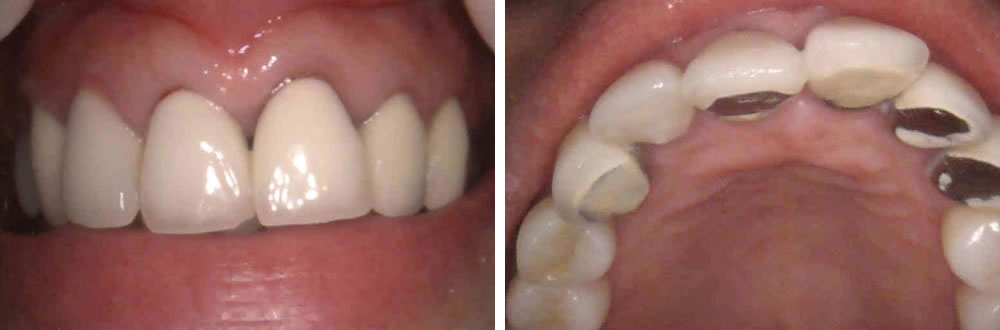

破折した前歯を抜歯してインプラントで治療した症例

年齢

40代

性別

男性

症例を見る